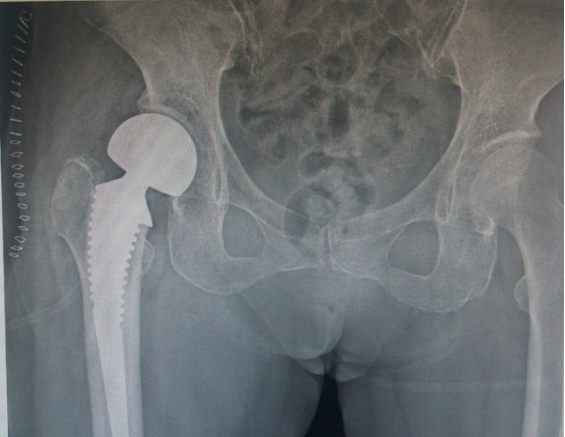

4.关节置换术

老年人关节内骨折合并骨质疏松症时,软骨下骨质量差,骨折块易嵌入关节面,解剖复位困难,骨折复位在下地负重或关节活动时难以维持,因此内固定治疗效果不佳。此时可酌情选择关节置换治疗,能够获得更好的预后。当骨折未累及关节面,但存在股骨头缺血性坏死风险时,例如股骨头下骨折或肱骨近端骨折,关节置换术的疗效于内固定[27][28][29]。随着反肩关节置换术的出现,越来越多的骨科医生选择关节置换术治疗复杂的肱骨近端骨折,获得了良好的治疗效果而肘关节置换术已成为复杂骨质疏松性肱骨远端骨折的常规治疗手段,临床研究也验证了其优良且可靠的治疗效果[28]。因此,当骨质疏松性骨折骨质量差,骨折碎片较小时,人工关节置换术应首先考虑。